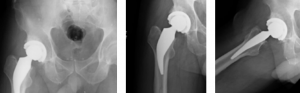

A 59-year-old Caucasian male weighing 192lbs diagnosed with osteo/degenerative arthritis received Advita’s Alteon Neck Preserving stem with a Bioloxdelta femoral head and InteGrip acetabular shell. The patient went under spinal anesthesia using a direct anterior surgical approach with an incision size of 9cm. There was an estimated blood loss of 200cc, and surgery duration was 63 minutes. The patient was discharged after one day postoperative with a walker to in home care for rehabilitation.

Pre-Op AP Pelvis

Harris Hip Score 60 (max=100) | Oxford Hip Score 25 (max=48)

6-Week Post-Op

Harris Hip Score 96 (max=100) | Oxford Hip Score 42 (max=48)

3-Month Post-Op

Harris Hip Score 96 (max=100) | Oxford Hip Score 37 (max=48)

1-Year Post-Op

Harris Hip Score 97 (max=100) | Oxford Hip Score 44 (max=48)

CONCLUSION

Previous to his total hip replacement, this patient presented with low Harris Hip and Oxford Hip scores. The outcomes of this case continue to be followed annually, and this patient is satisfied with his hip replacement. One year after his surgery, his scores increased by more than 38.1 percent on the Harris Hip and 43.2 percent on the Oxford Hip. The direct anterior approach used in this surgery has been associated with faster functional recovery than the posterolateral approach. •